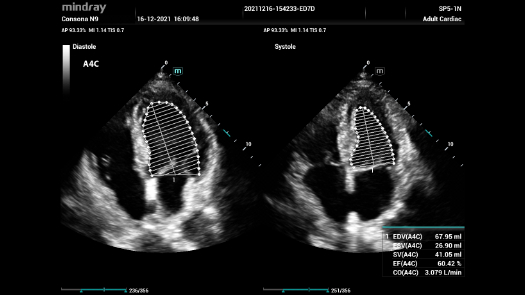

Bez wzgl?du na to, czy pracujesz w szpitalu, przychodni, czy u?ywasz ultrasonografu do badaÅ ogÃģlnych, w opiece zdrowotnej kobiet lub w badaniach sercowo-naczyniowych, w serii Consona znajdziesz bardzo pot??ne narz?dzia, aby utrzyma? si? w czo?Ãģwce.

Galeria obrazÃģw